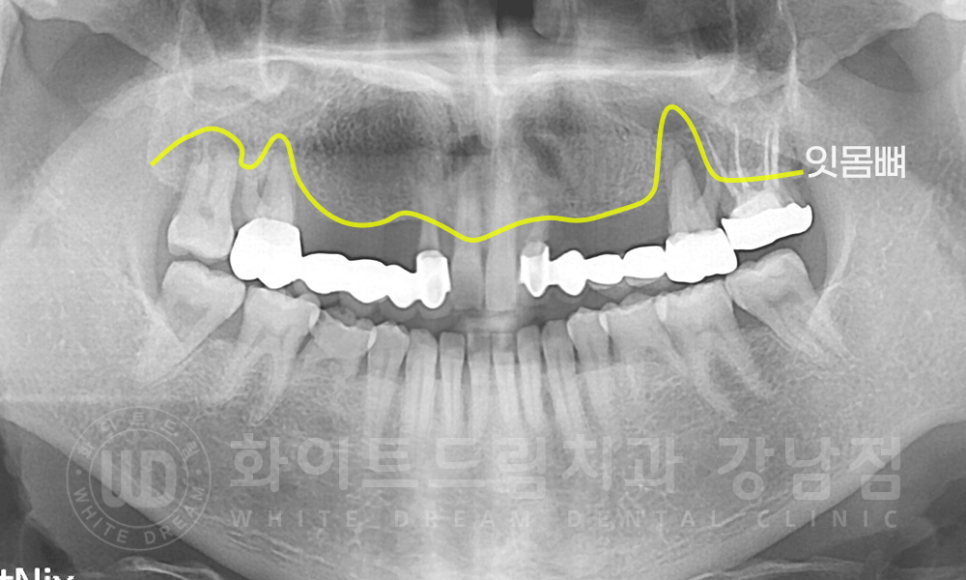

사실 보철의 밑 부분까지 청소한다는 것은 어렵기 때문에 오랜 기간 브릿지를 사용하신 분들은

브릿지 주변에 잇몸 염증이 이렇게 심하신 경우가 많답니다.

유치는 별 이상이 없었기에 브릿지 부분의 치료만 진행했는데요.

브릿지 주변 잇몸에 만성 치주염이 있는 것으로 확인되었고,

여태까지 브릿지를 지탱해 준 지대치 또한 수명을 다했기에

해당 브릿지 철거 및 지대치 발치, 염증 치아 발치를 진행하기로 했습니다.